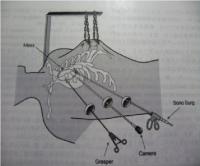

肺癌その進行度により病期IからIV期に分類されます。また、肺癌は非小細胞肺癌(腺癌、扁平上皮癌、大細胞癌、腺扁平上皮癌、腺様嚢胞癌、粘表皮癌など)と小細胞肺癌に分類することができます。どの病期または組織型にあてはまるかにより治療法は異なります。非小細胞肺癌の場合、I期、II期、IIIA期の一部であれば手術療法の適応となります。なかでもI期症例は胸腔鏡手術の良い適応とされています。当科では癌の進展状況、全身状態、心肺機能など十分考慮した上で、手術可能であるか、術式をどうするか(胸腔鏡下手術の適応など)さらには術後補助化学療法を行うかを呼吸器内科医と連携をとりながら肺癌を治療していきます。また、当科は胸腔鏡手術いわゆる内視鏡手術を積極的に行い、患者さんの体に優しい手術を得意としています。当院で施行した胸腔鏡下右肺葉切除術+縦隔リンパ節郭清の術後の創部の写真を以下に示します。まず、5cm大の小開胸創のみの胸腔鏡手術で、患者さん側に対して侵襲が小さく、創部痛も極めて最小限に抑えます(Single Incision Thoracoscopic surgery:SITS写真1)。さらに、胸腔内の状況に応じて3つないし4つのポート孔から手術を行う(いわゆる完全胸腔鏡手術:Pure Video Assisited Thoracoscopic surgery:Pure VATS写真2)または、小開胸創(5から 10cmサイズ)と1つないし2つのポート孔から行う手術(Video Assisted Thoracoscopic Surgey:VATS写真3)を行います。当科での胸腔鏡手術は1)手術の大部分がモニター下で、2)小開胸創のサイズは5から10cm(術者の手が胸腔内に挿入不能なサイズ)、3)肋骨切除がなされない手術と定義しています。胸腔鏡下手術とは胸腔鏡(カメラと光源を兼ね備えた器具)を用いて視野を確保し、胸腔鏡や自動縫合器、鉗子などを挿入し、手術を行う手術法です。呼吸器外科での胸腔鏡手術の厳密な定義はいまだ定めれてはいませんが、当科では患者さんに対して上記の術式で最大限低侵襲になるよう心掛けております。また、進行癌に対しても限りなく完全切除(腫瘍を完全に切除すること)を目指して手術を行います。

胸腔鏡手術の実際(右肺上葉切除時の自動縫合器使用例)